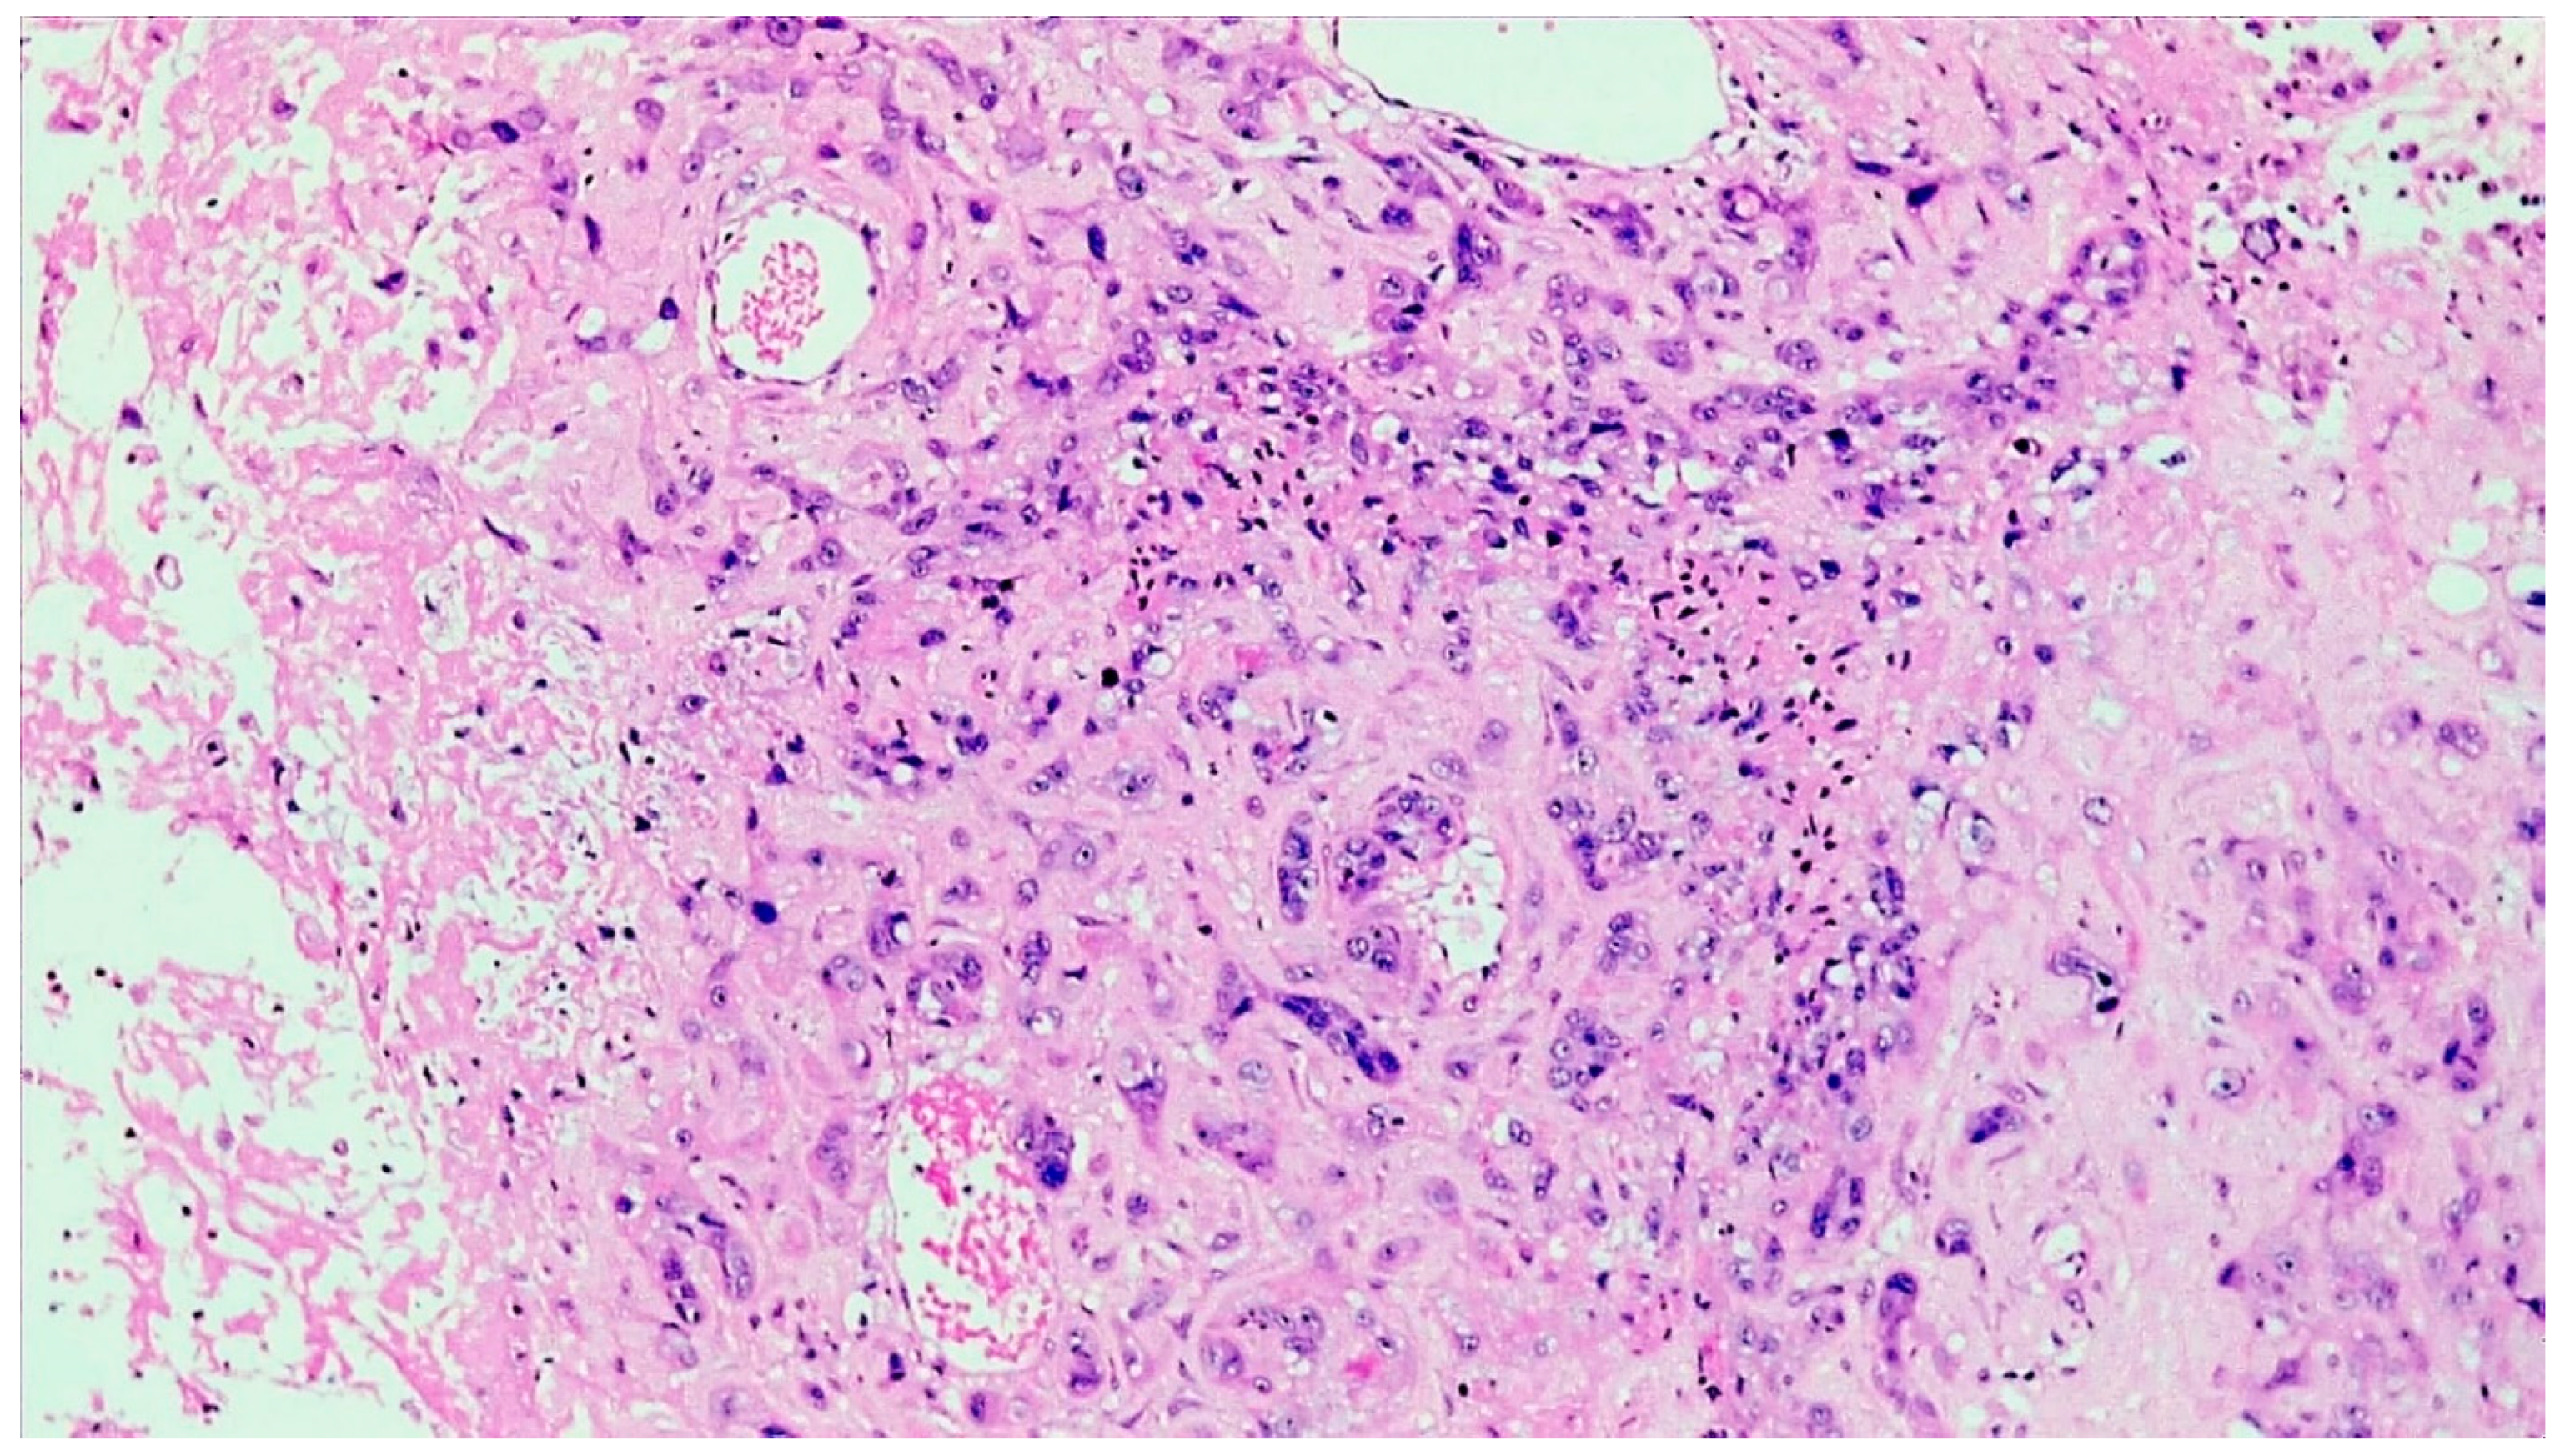

2. Case Presentation